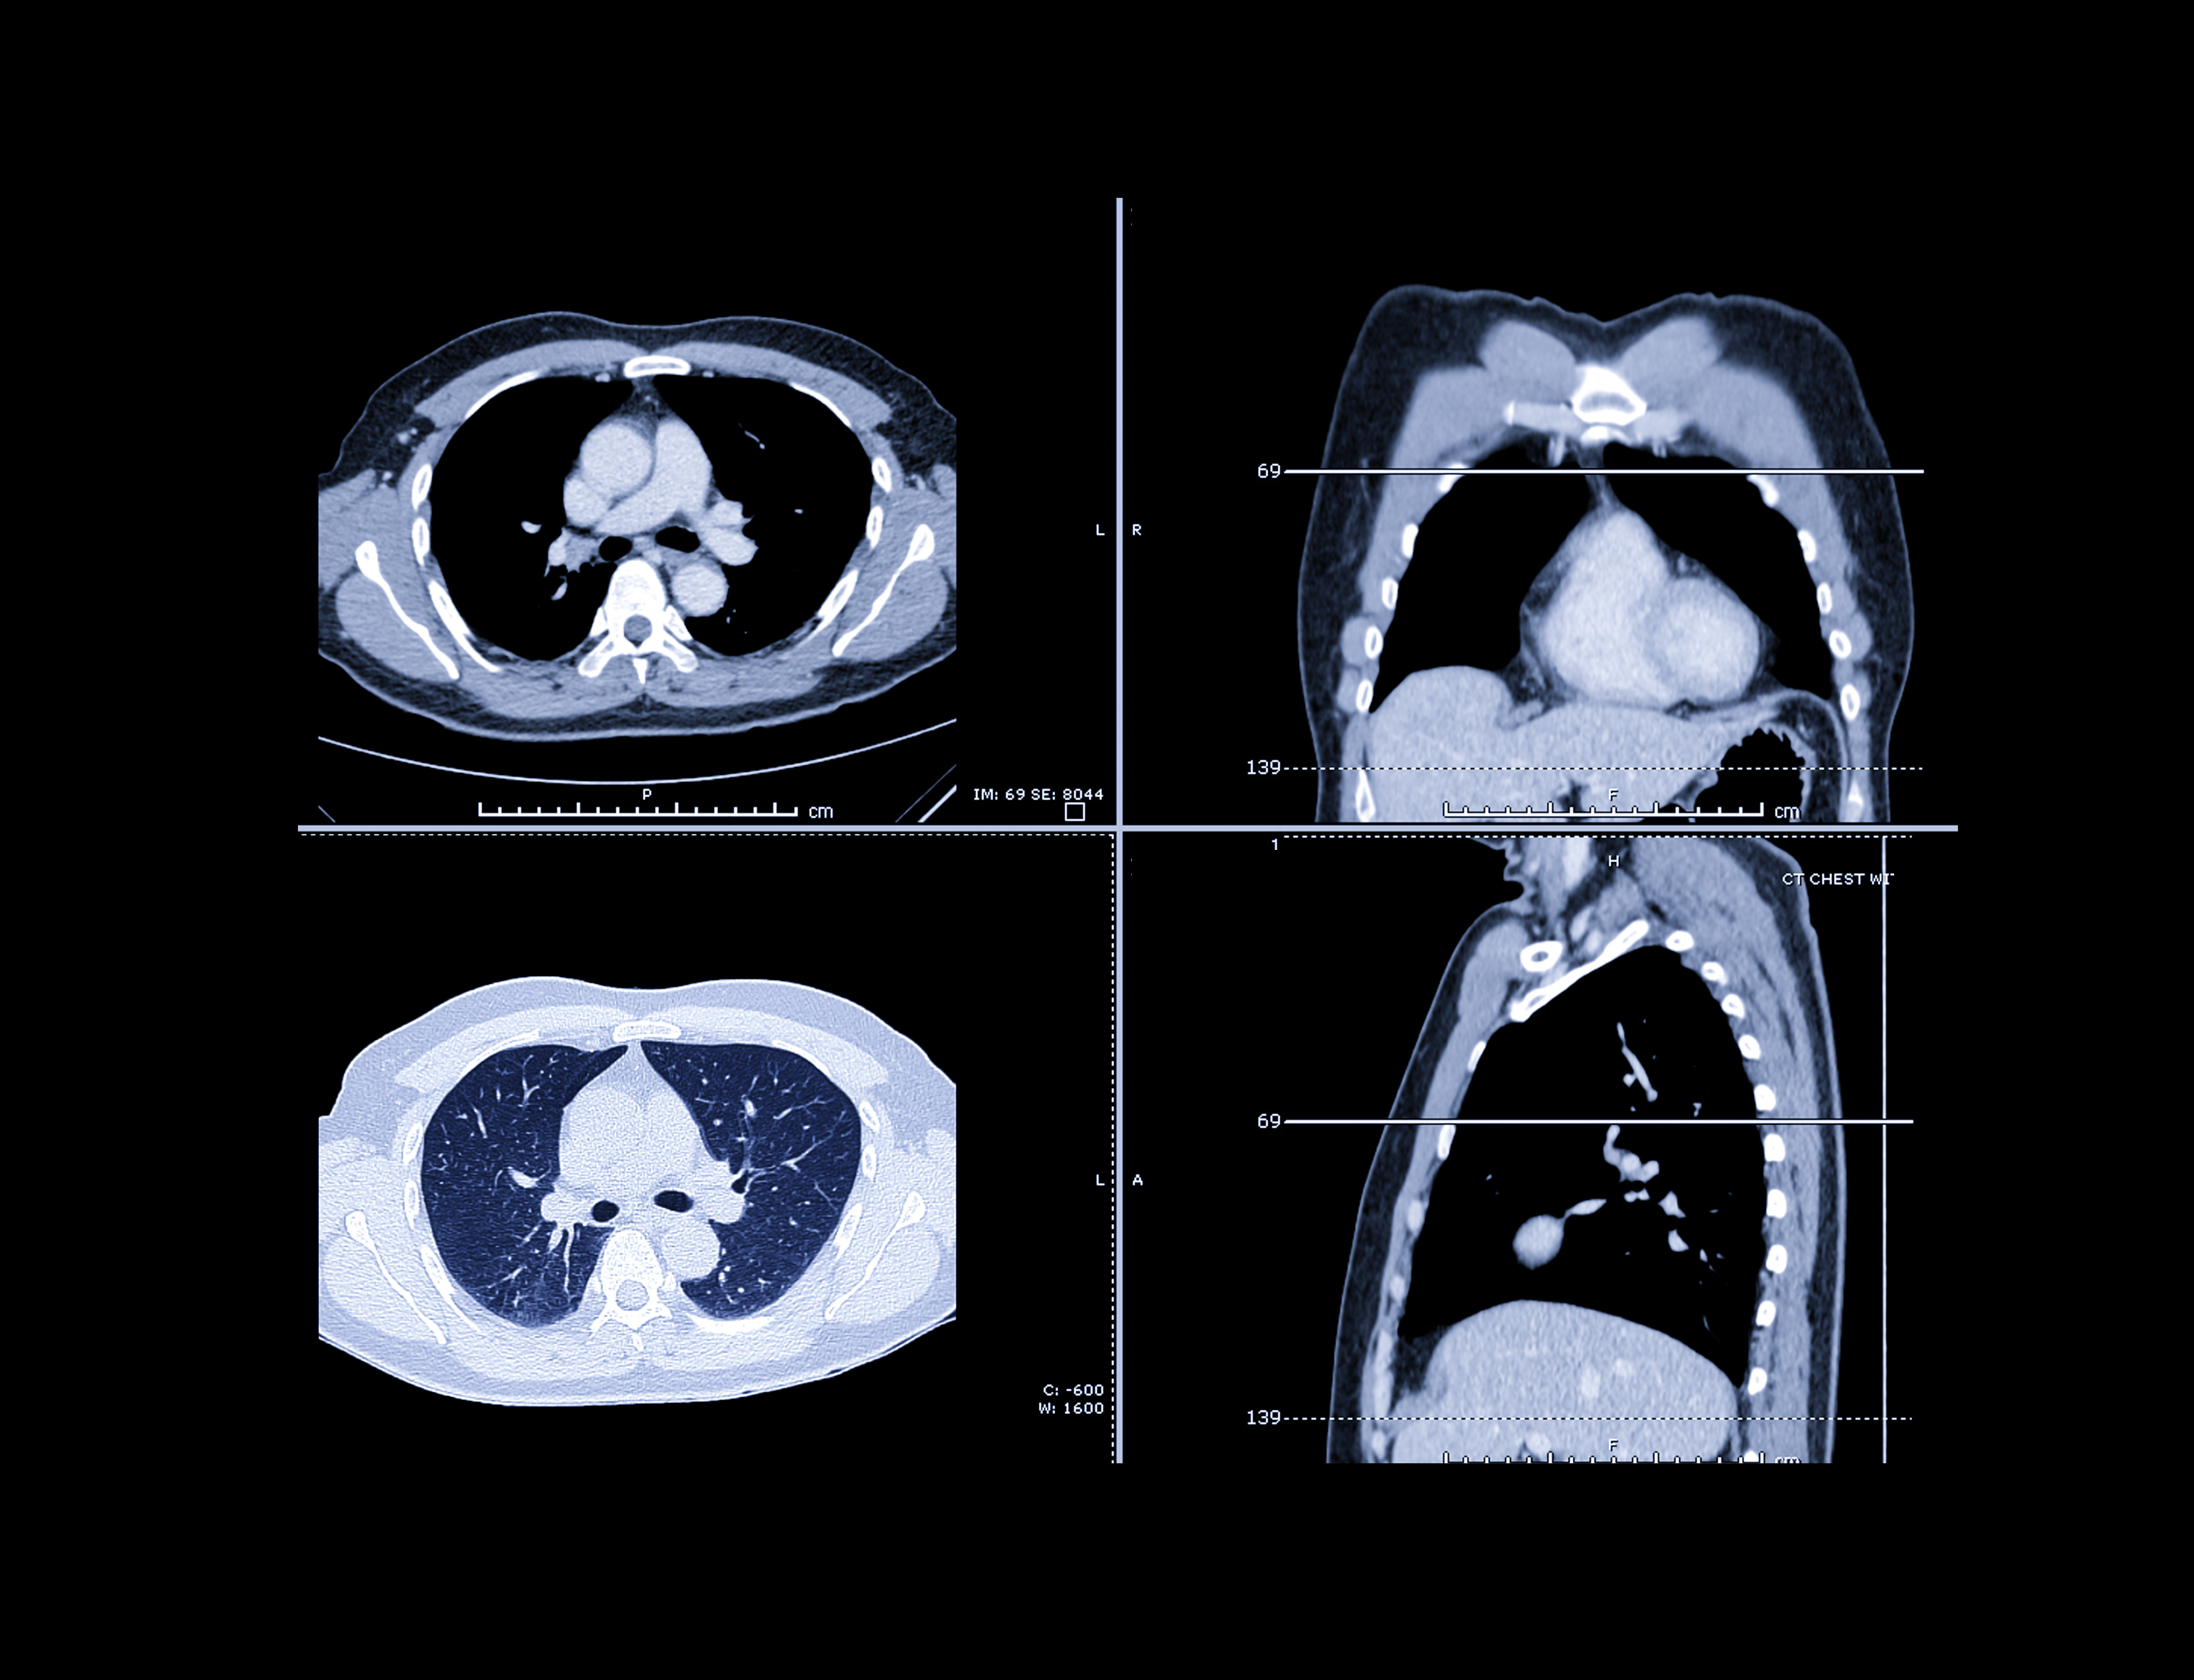

CT may be the gold standard for diagnosing complicated pneumonia, but lung ultrasound may be a viable first choice for patients in the emergency department, according to a study published on February 14 in Ultrasound in Medicine & Biology.

Timely chest imaging is critical for patients who may have pneumonia, as a delay in antibiotic treatment could result in worse outcomes. Although CT is the ideal modality for diagnosing pneumonia, it's not always timely and feasible in an emergency setting. The researchers wondered whether bedside ultrasound scans could be a viable first-step alternative.

To find out, they enrolled 125 patients with suspected pneumonia who visited a university hospital between July 2015 and April 2016. Trained clinicians performed both bedside lung ultrasound and posteroanterior and lateral chest x-rays for all patients. They also used CT for 61 patients who needed further evaluation.